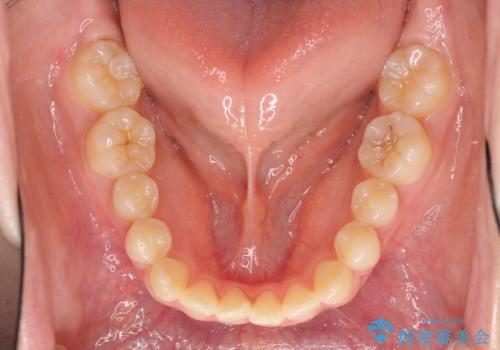

- 前歯のオープンバイトを気にして来院された患者様です。

上下前歯の前後位置が大きくずれていたため、上顎左右第一小臼歯2本を抜歯してワイヤー装置による矯正治療を行うこととしました。